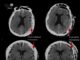

Fahamkan: Individu Ketujuh Mencapai Status Bebas HIV Jangka Panjang

Fahamkan telah menjadi individu ketujuh yang diketahui mencapai status bebas HIV jangka panjang selepas menjalani pemindahan sel stem.

Apa yang menjadikan kes ini luar...